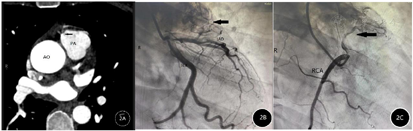

辅助检查:入院后查血常规:WBC 11.1×109/L,肌酸激酶同工酶、肌酸激酶、凝血象、肌钙蛋白Ⅰ、甲状腺功能等未见异常。心电图提示下壁、前壁导联压低(图1A)。心脏超声未见明显异常。为明确患者运动时是否存在心肌缺血,遂行心肺运动试验,结果显示运动达最大负荷及恢复时出现胸闷症状,心电图Ⅱ、Ⅲ、AVF、V4-V6导联ST段压低0.1 mV(图1B)。冠状动脉CT血管成像及冠状动脉造影显示(图2):左前降支、右肺动脉圆锥之-肺动脉瘘,右肺动脉圆锥之直接起源自右冠状动脉窦,冠状动脉管腔未见狭窄。

我们的病例极为罕见,因为大多数报道的病例是冠状动脉前降支(left anterior descending,LAD)和肺动脉之间的瘘管,但在本案例中,肺动脉与左右冠状动脉形成多条瘘管,并且表现为心绞痛症状,患者经手术治疗后症状明显缓解,术后5个月复查冠状动脉CTA未见冠状动脉-肺动脉瘘。在表现为心绞痛的患者中,冠状动脉造影可提供冠状动脉狭窄程度、解剖位置、瘘管和动脉瘤等信息,还有助于进行适当的手术评估。由于CPAF在临床上罕见,在表现心绞痛和劳累后呼吸困难的患者中容易被忽略,因此在这类患者中更应该明确疾病的原因,不能忽略类似的少见或罕见的疾病,以免造成漏诊。